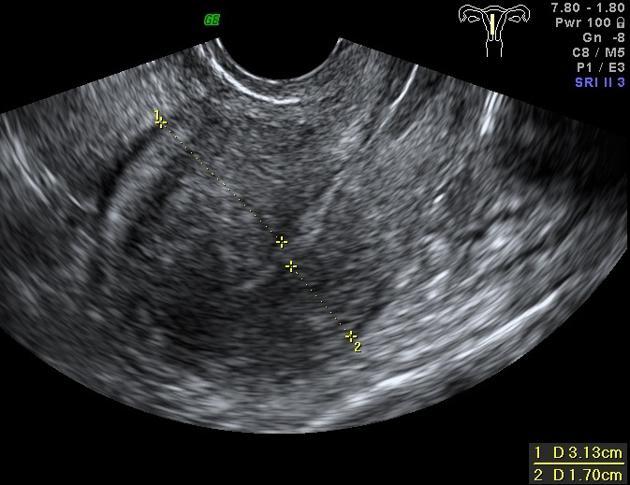

자궁 근종을 초음파로 보았을 때는 가로, 세로, 부피의 형태가 가늠할 수 있다.(아래 사진 좌) 이에 반해 선근증은 자궁 내막에 생겨 자궁벽 내로 침투하기 때문에 자궁 근종에 비해 근종 근처에 혈관들이 많이 밀집되어 있다. 그래서 선근종을 검사할 때는 초음파로 정확한 형태를 파악하기 힘들다고 한다. 일반적으로는 막대기처럼 길쭉하게 뻗어있는 모습을 보인다. 산부인과에서 선근증을 진단할 때는 먼저 초음파로 혈관들이 많은지 여부를 먼저 살펴보고 MRI나 조직 검사로 구체적인 상태를 검사한다고 한다.

자궁근종 초음파.jpg